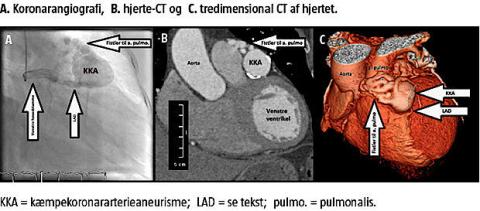

Ved KAG fandt man ingen betydende aterosklerose, men udtalt ektasi af venstre koronararteries hovedstamme og proksimale del af ramus interventricularis anterior (LAD). Ramus circumflexus (LCX) og højre koronararterie (RCA) var normale. Undersøgelsen var dog suboptimal, og den distale del af LAD kunne ikke fremstilles. Der blev derfor efterfølgende udført hjerte-CT, som ligeledes viste normale forhold i RCA og LCX, mens venstre koronararteries hovedstamme og den proksimale del af LAD var lang og ektatisk med en diameter på 8 mm. Ud for afgangen af første diagonal fandt man et anurisme med randforkalkning og en diameter på 35 mm. Fortil i anurismet sås et »ormegårdslignende« fistelsystem med kommunikation til a. pulmonalis. Den distale del af LAD efter aneurismet var uden stenoser.

KAG og hjerte-CT afslørede et anuriseme og et »ormegårdslignende« fistelsystem med kommunikation til a. pulmonalis. Den mangelfulde visualisering af den distale LAD ved KAG skyldes formentlig en reduceret kontrastkoncentration, der her var forårsaget af fortynding i aneurismet. Der blev ikke påvist klinisk betydende shunt til lungekredsløbet, og der blev ikke fundet objektive tegn på myokardieiskæmi under belastning (myokardiescintigrafi).